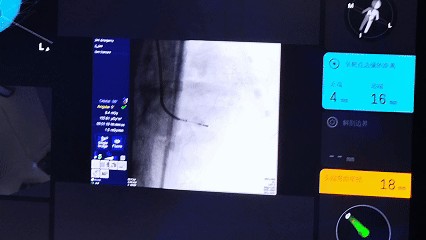

3 確認(rèn)消融: 利用機(jī)器人系統(tǒng)的實(shí)時(shí)影像與定位功能,確認(rèn)導(dǎo)管位置與病灶關(guān)系。

3 啟動(dòng)治療: 在統(tǒng)一的操作視野下,一鍵啟動(dòng)微波消融,并可結(jié)合影像進(jìn)行實(shí)時(shí)效果評(píng)估。